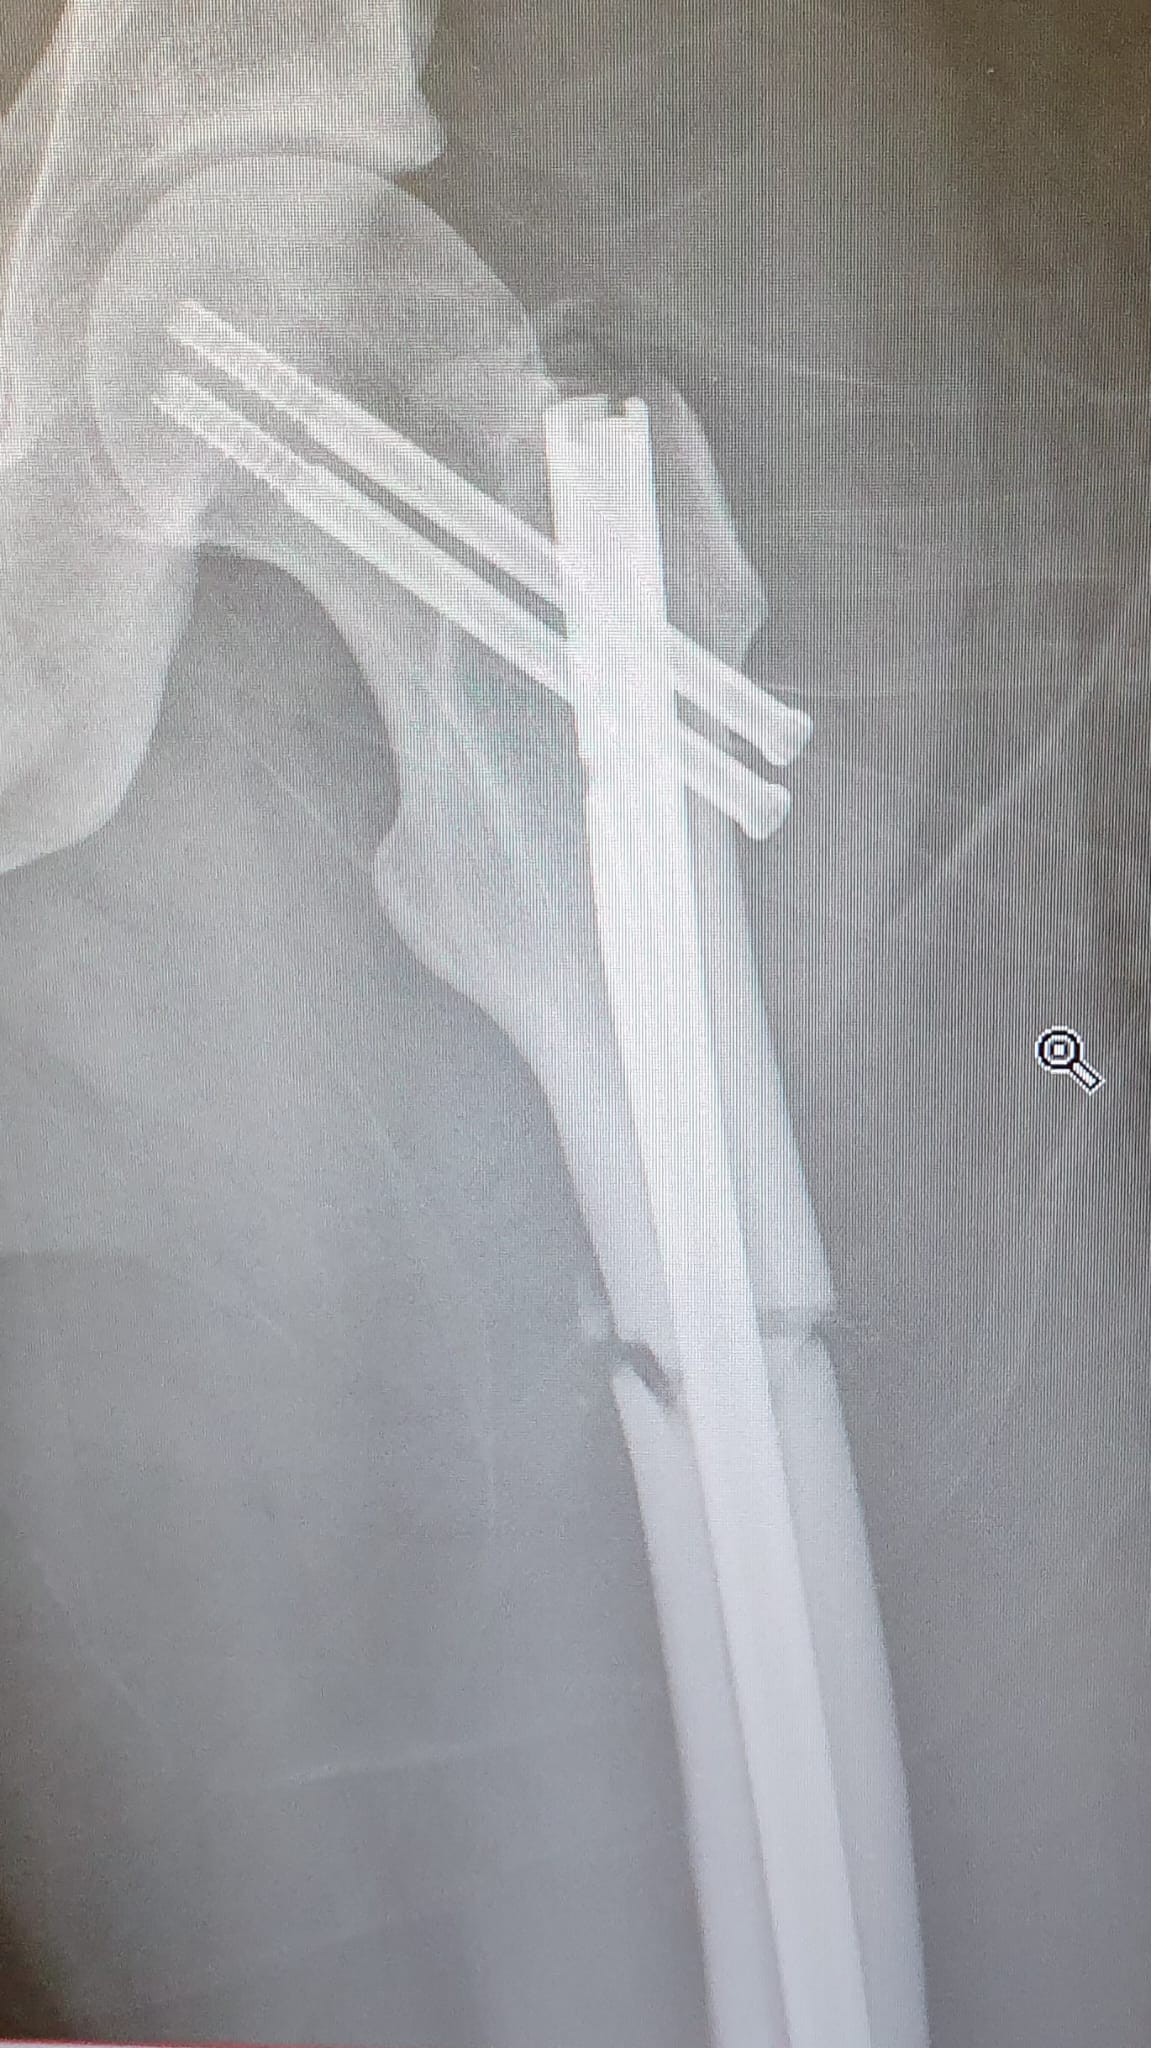

This can happen with femoral nails even under normal weight bearing and if the operating surgeon had just put a distal locking screw in the dynamic hole (the oblong hole just under the circular hole which the screw has broken in, known as the static hole) then this wouldn't be an issue as the nail would dynamise and compress the fracture site and would actually lead to continued callus formation and healing. But since they didn't do that simple thing they now need to go back in and put another screw in. Waste of time and increases risk of infection. The reduction of the fracture is great though and there is callus formation so it is healing, I don't know why they didn't bother putting that 2nd screw in.

t. orthopaedic surgeon (I can't find an XR which doesn't have a knee replacement in it but the principle is the same).

Based. Here's one I did a few years with a mate of mine when we were juniors, this was a lot more fucked and the patient never came back for follow up so I don't know what happend to them for sure, hopefully they ar fine.

>>